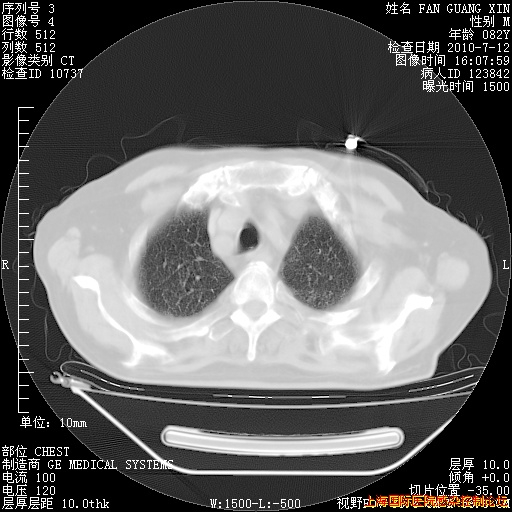

今天复查CT

今天CT

整整相隔30天的肺部CT好像有所好转啊。甲强龙减量第3天,需要观察体温。

海管,自昨日你和我通完话后,不知您岳父消化道症状有无缓解?体温怎样?阅读7.12日胸部ct,个人认为目前激素治疗是有效的,甲强龙减量是适宜的。因在抗痨治疗,需密切观察肝功、肾功能和血常规。不过,老年、长期住院和大量使用激素,很担心菌群失调发生